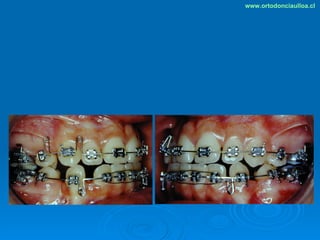

Este documento presenta dos casos clínicos de pacientes que recibieron tratamiento de ortodoncia. El primer caso fue de una paciente femenina de 14 años con apiñamiento dental y mordida cruzada que fue tratada mediante extracción de premolares y alineamiento dental. El segundo caso fue de un paciente masculino de 14 años con clase II esqueletal y desarmonía dentomaxilar que fue tratado con extracción de premolares y corrección de mordida. Ambos casos mostraron mejoría después de 3 años de tratamiento.